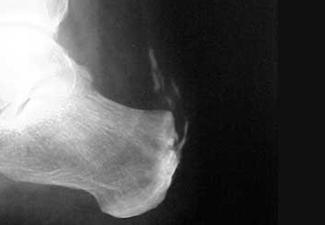

Patología insersional del tendón de aquiles.

Calcificaciones intratendinosas del aquiles.